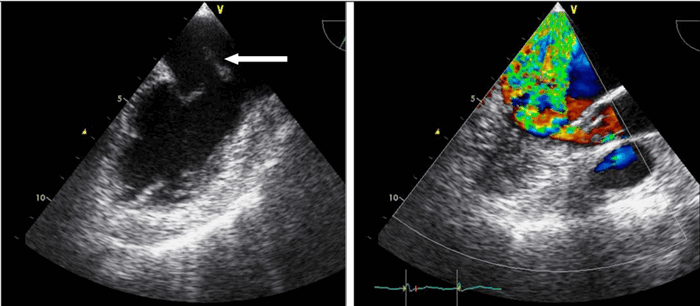

4. Чреспищеводная эхокардиография (моно-, би-, и мультиплановая). Исследование сердца через пищевод с использованием специальных датчиков. Информативность метода очень высокая. Противопоказанием служит наличие стриктуры пищевода.